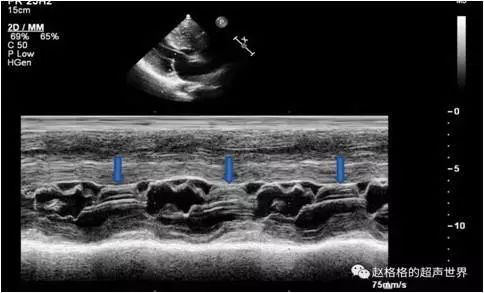

显示左心室壁显著增厚,心室间隔较心室后壁更为肥厚,左心室腔小,流出道狭窄和心脏收缩时二尖瓣前瓣叶向前移位(SAM征)。

超声心动图

SAM征小知识